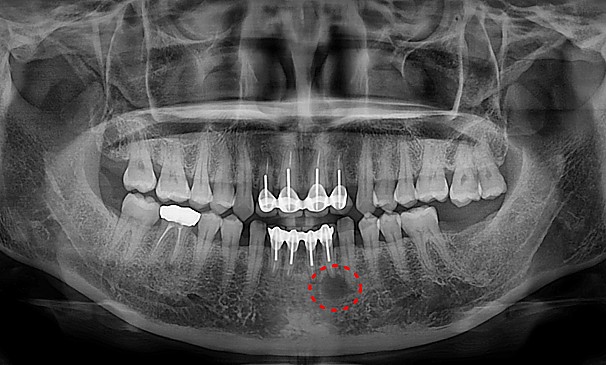

병든뿌리절제술

배OO님 전후사진 | 치료 기간 : 1주

치료 전

치료 후

김OO님 전후사진 | 치료 기간 : 1주